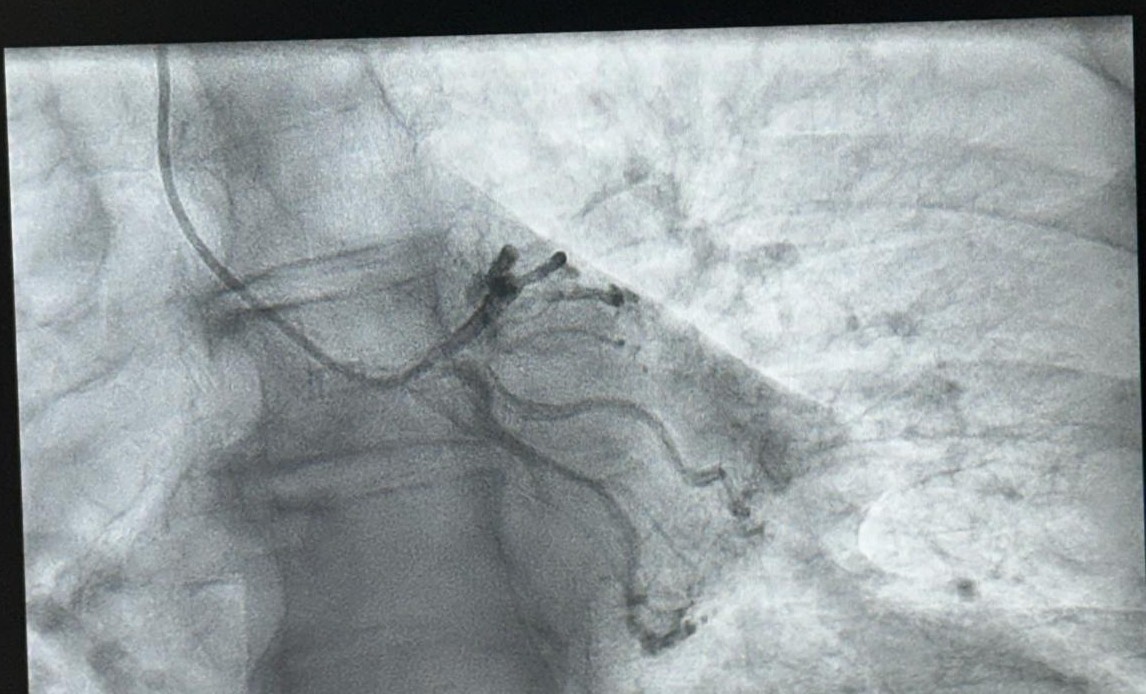

Sot u realizua me sukses koronarografia e parë pranë Spitalit Katolik Zoja e Këshillit të Mirë, duke shënuar kështu fillimin e një shërbimi të rëndësishëm për spitalin tonë.

Salla e re moderne e angiografisë me pajisjet më të avancuara garanton precizion të plotë diagnostik dhe cilësi të shkëlqyer të trajtimit për pacientët tanë sipas standardeve evropiane.

- Procedura e koronarografisë diagnostike u realizua me sukses nga ekipi ynë profesionist: Dr. Aurel Demiraj, Dr.Alk Shehu, Dr. Ervin Bejko dhe ekipi i infermierëve.